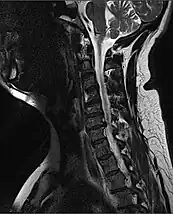

| Other names: Spinal trauma | |

![]() | |

| MRI of fractured and dislocated neck vertebra that is compressing the spinal cord | |

A radiographic evaluation using an X-ray, CT scan, or MRI can determine if there is damage to the spinal column and where it is located.[15] X-rays are commonly available[60] and can detect instability or misalignment of the spinal column, but do not give very detailed images and can miss injuries to the spinal cord or displacement of ligaments or disks that do not have accompanying spinal column damage.[15] Thus when X-ray findings are normal but SCI is still suspected due to pain or SCI symptoms, CT or MRI scans are used.[60] CT gives greater detail than X-rays, but exposes the patient to more radiation,[62] and it still does not give images of the spinal cord or ligaments; MRI shows body structures in the greatest detail.[15] Thus it is the standard for anyone who has neurological deficits found in SCI or is thought to have an unstable spinal column injury.[63]